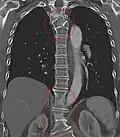

Several congenital block vertebrae in the transition from the thoracic to the lumbar spine and hemivertebrae. -

Congenital block vertebra in the lumbar spine (partial vertebrae 3 and 4). The rear portion of the disc still exists. -